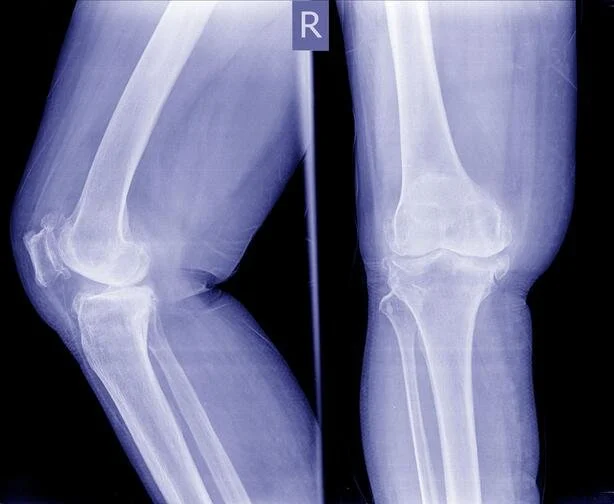

Клинично артрозата се проявява със ставна болка при натоварване, сутрешна скованост, постепенно ограничаване на движенията и в по-напреднали стадии – деформации. Най-често са засегнати коленете и тазобедрените стави.

Смяна на колянна става – пълно ръководство

https://www.dryordanov.com/publikacii-d-r-yordanov/rukovodstvo-protezirane-kolyano